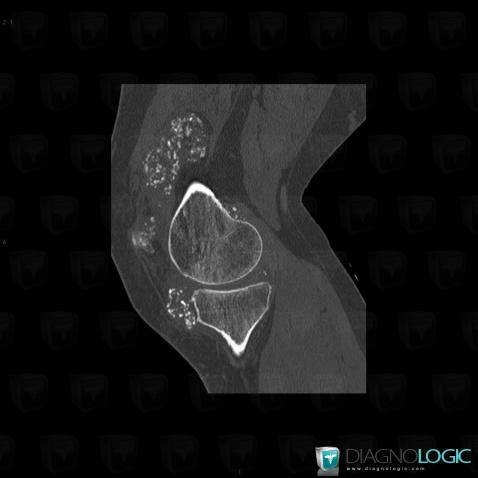

Ostéochondromatose synoviale, Fémur -inférieur, Tibia -supérieur, Scanner

- Diagnostic Ostéochondromatose synoviale, Localisation(s) Fémur - 1/3 inférieur, comportant les gammes Ostéolyse corticale, Erosion corticaleTibia - 1/3 supérieur, comportant les gammes Ostéolyse corticale, Erosion corticaleAutres parties molles/nerfs - Genou, comportant les gammes Calcifications des parties molles, Masse des parties molles avec ostéolyse, Masse calcifiée des parties molles, Masse des parties molles juxta articulaires